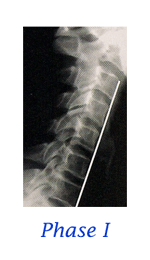

Stages of Spinal Degeneration

When it comes to the spine, the average person’s only interest is with PAIN. Statistics claim that each of us will be disabled with low back pain at least twice in our lives. We may, on average, only miss a couple days work, but many people find back pain to be a lifelong “challenge”. For too long, and too often, the general public has been coerced into thinking that surgery is the only answer for a diagnosis of “slipped disc”. But what is a “slipped disc”? Most people think it is like biting into a tuna sandwich and having all the tuna go out the backside. Oops! That must be really bad! Then again, you may have been told that your diagnosis is a “bulged disc”, “protruding disc”, “herniated disc”, “degenerating disc”, “Fragmenting disc” or maybe “degenerative disc disease”. How confusing can these disc problems be? VERY CONFUSING! . . . continue with Do You Have a "Slipped Disc"?